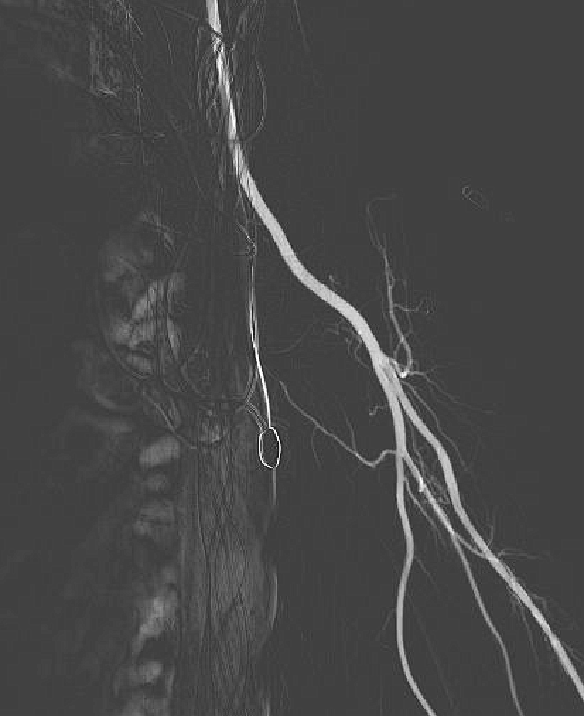

NeuronMax头端顺应性良好【白箭头】,球囊扩张支架充分

动脉长鞘怎么置入健谈卒中|张志勇教授:伐竹取道,另辟蹊径  一例桡动脉入路经NeuronMax长鞘行左侧锁骨下动脉支架置入治疗_https://www.jmylbn.com_新闻资讯_第12张